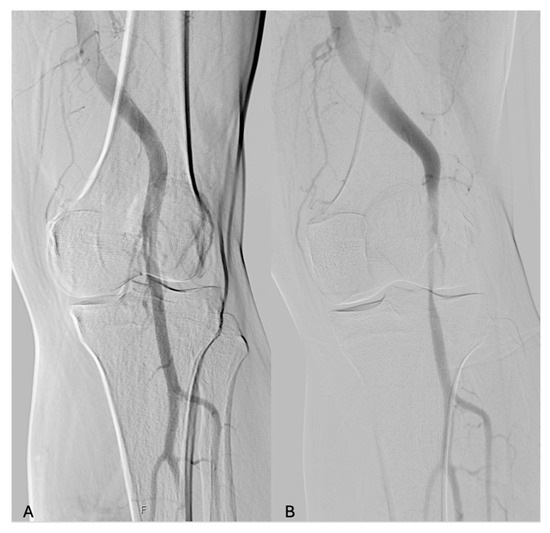

The sensitivity to the detection of PAES was 96.2% for DSA with dynamic maneuvers, 54.5% (12 limbs) for MRA, and 51.7% (29 limbs) for CTA (Figure 1 and Figure 2).

Figure 1. Digital subtraction angiography in a patient affected by PAES with popliteal artery stenosis after dynamic maneuvers. (A) neutral position; (B) dynamic maneuvers of dorsiflexion of the feet.